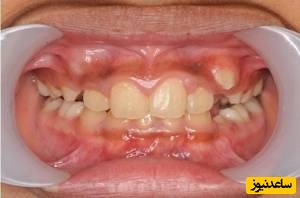

برای کل جمعیت شیوع دندان اضافی 0.15 تا 3.9 درصد برآورد می شود. میزان شیوع آن برای مزیودنس (دندان اضافی جلوی دهان) معمولاً بین 0.15 تا 1.9 درصد می باشد که بسته به نژاد متفاوت است. مزیودنس دو فک بالا شایع تر است (82 درصد موارد مزیودنس به فک بالا مربوط می شود). دندان اضافی ممکن است به صورت تکی یا چند تایی دیده شود. یک سوم افرادی که مزیودنس دارند، دندان اضافی دیگری نیز دارند. تنها حدود 25 درصد مزیودنس ها در نهایت از لثه کامل بیرون میزنند.

گاهی نیاز است که دندان اضافه کشیده شود. برای مثال اگر دندان به طور جزئی یا به طور کامل پوسیده شده باشد، پزشک می تواند تصمیم بر خروج آن از دهان بگیرد. وی دندان را به آرامی به عقب و جلو حرکت می کند تا آن را از ریشه جدا نماید.در بعضی موارد بیمار ممکن است یک یا چند دندان اضافی در فک داشته باشدکه اصطلاحا به آن دندان supernumerary می گویند. بیمار معمولا دارای تنها یک دندان اضافه می باشد اما در برخی موارد ممکن است چندین دندان اضافه وجود داشته باشد که در این صورت به آن hyperdontia می گویند.